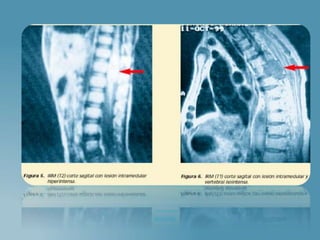

 Encéfalo

 Meninges

 Cráneo

 Medula Espinal

 Columna